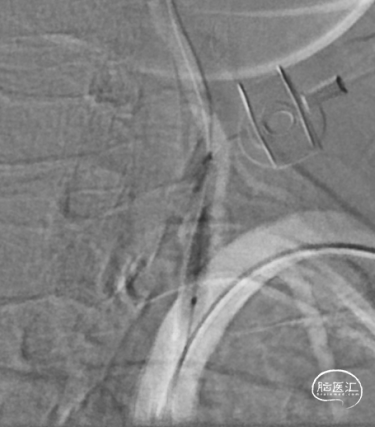

8F导引导管到达锁骨下动脉。

微导丝通过椎动脉起始处狭窄段,到达椎动脉V3段。

沿微导丝送入2.5mm*15mm球囊预扩张狭窄处。